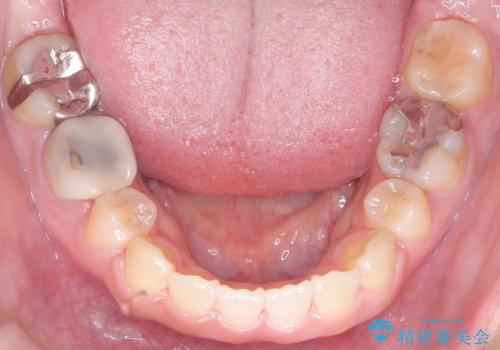

- 口元が出ている(突出している)ことを気にされて来院されました。精密な検査の結果、前歯を大きく後退させるスペースが必要と診断。患者様の**「前歯を下げたい」という強いご要望に応えるため、上下左右の第一小臼歯を抜歯し、そのスペースを利用して前歯を奥へ移動させる治療計画を立案しました。また、人目を気にせず治療できるよう、上顎に裏側矯正、下顎に表側矯正を組み合わせたハーフリンガル矯正**を提案しました。

今回の矯正治療では、前歯を大きく後退させるスペースを確保するため、計画通り上下左右の第一小臼歯を抜歯しました。装置には、上顎には目立たない裏側矯正(舌側矯正)を、下顎には透明な審美ブラケットを使用するハーフリンガル矯正を採用しました。抜歯によってできたスペースを最大限に活用し、前歯を効率よく後方へ移動。治療の結果、口元の突出感が大幅に解消され、Eライン(横顔の美しさの基準)も改善しました。人目を気にすることなく治療を完遂し、自信の持てる美しい横顔を獲得していただけました。